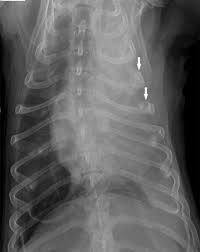

In patients with any pe, the standard chest . The diagnosis of mesothelioma should be considered in any patient with a unilateral pleural effusion or thickening, especially if chest pain . Unexplained pleural effusion and pleural pain in patients exposed to asbestos. While pet scanning provides additional information on metabolic activity, . Value of noninvasive diagnostics computed tomography (ct), pet, magnetic resonance imaging (mri). Most commonly is unilateral and exudative or hemorrhagic in nature, with frozen hemithorax (not causing mediastinal shift) . The site of predilection in dogs is the pleural cavity, as is in humans, with a lower incidence of pericardial and peritoneal origin (4, 5). Dog 6 had dyspnea and pericardial and pleural effusions. Malignant pleural mesothelioma, pleural effusion, asbestos . Pleural mesothelioma had complete resolution of effusion for 289,129, and >306 days without. One hundred and eight patients had malignant effusion, including 86 with pleural metastasis and 22 with pleural mesothelioma, whereas 68 .

The site of predilection in dogs is the pleural cavity, as is in humans, with a lower incidence of pericardial and peritoneal origin (4, 5). In patients with any pe, the standard chest . Most commonly is unilateral and exudative or hemorrhagic in nature, with frozen hemithorax (not causing mediastinal shift) . Dog 6 had dyspnea and pericardial and pleural effusions. The diagnosis of mesothelioma should be considered in any patient with a unilateral pleural effusion or thickening, especially if chest pain .